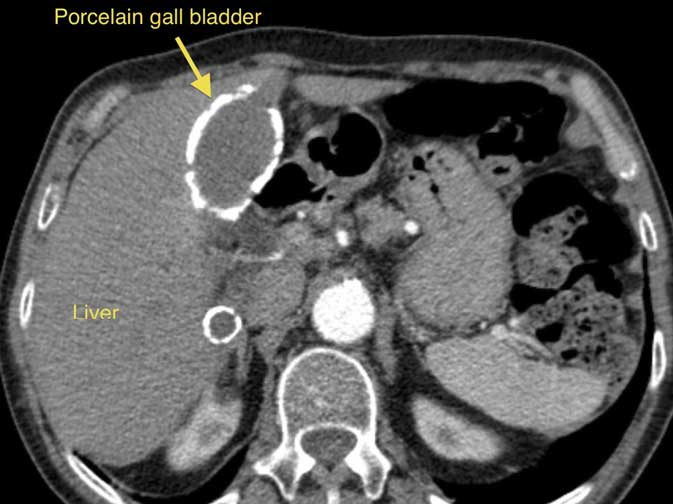

Calcium deposits in the wall of the gall bladder (a consequence of chronic inflammation), described as Porcelain gall bladder, increase the risk of gall bladder cancer. The picture on this page shows a CT scan, with a porcelain gall bladder clearly visible (you can click on the picture to enlarge it).